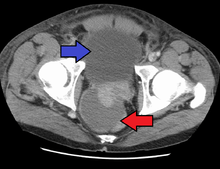

Acute prostatitis is relatively easy to diagnose due to its symptoms that suggest infection. The organism may be found in blood or urine, and sometimes in both.[1] Common bacteria are Escherichia coli, Klebsiella, Proteus, Pseudomonas, Enterobacter, Enterococcus, Serratia, and Staphylococcus aureus. This can be a medical emergency in some patients and hospitalization with intravenous antibiotics may be required. A complete blood count reveals increased white blood cells. Sepsis from prostatitis is very rare, but may occur in immunocompromised patients; high fever and malaise generally prompt blood cultures, which are often positive in sepsis. A prostate massage should never be done in a patient with suspected acute prostatitis, since it may induce sepsis. Since bacteria causing the prostatitis is easily recoverable from the urine, prostate massage is not required to make the diagnosis. Rectal palpation usually reveals an enlarged, exquisitely tender, swollen prostate gland, which is firm, warm, and, occasionally, irregular to the touch. C-reactive protein is elevated in most cases.[3]

Antibiotics are the first line of treatment in acute prostatitis (Cat. I). Antibiotics usually resolve acute prostatitis infections in a very short time, however a minimum of two to four weeks of therapy is recommended to eradicate the offending organism completely.[4] Appropriate antibiotics should be used, based on the microbe causing the infection. Some antibiotics have very poor penetration of the prostatic capsule, others, such as Ciprofloxacin, Co-trimoxazole and tetracyclines such as doxycycline penetrate well. In acute prostatitis, penetration of the prostate is not as important as for category II because the intense inflammation disrupts the prostate-blood barrier. It is more important to choose a bacteriocidal antibiotic (kills bacteria, e.g. quinolone) rather than a bacteriostatic antibiotic (slows bacterial growth, e.g. tetracycline) for acute potentially life-threatening infections.[5] Severely ill patients may need hospitalization, while nontoxic patients can be treated at home with bed rest, analgesics, stool softeners, and hydration. Patients in urinary retention are best managed with a suprapubic catheter or intermittent catheterization. Lack of clinical response to antibiotics should raise the suspicion of an abscess and prompt an imaging study such as a transrectal ultrasound (TRUS).[6]